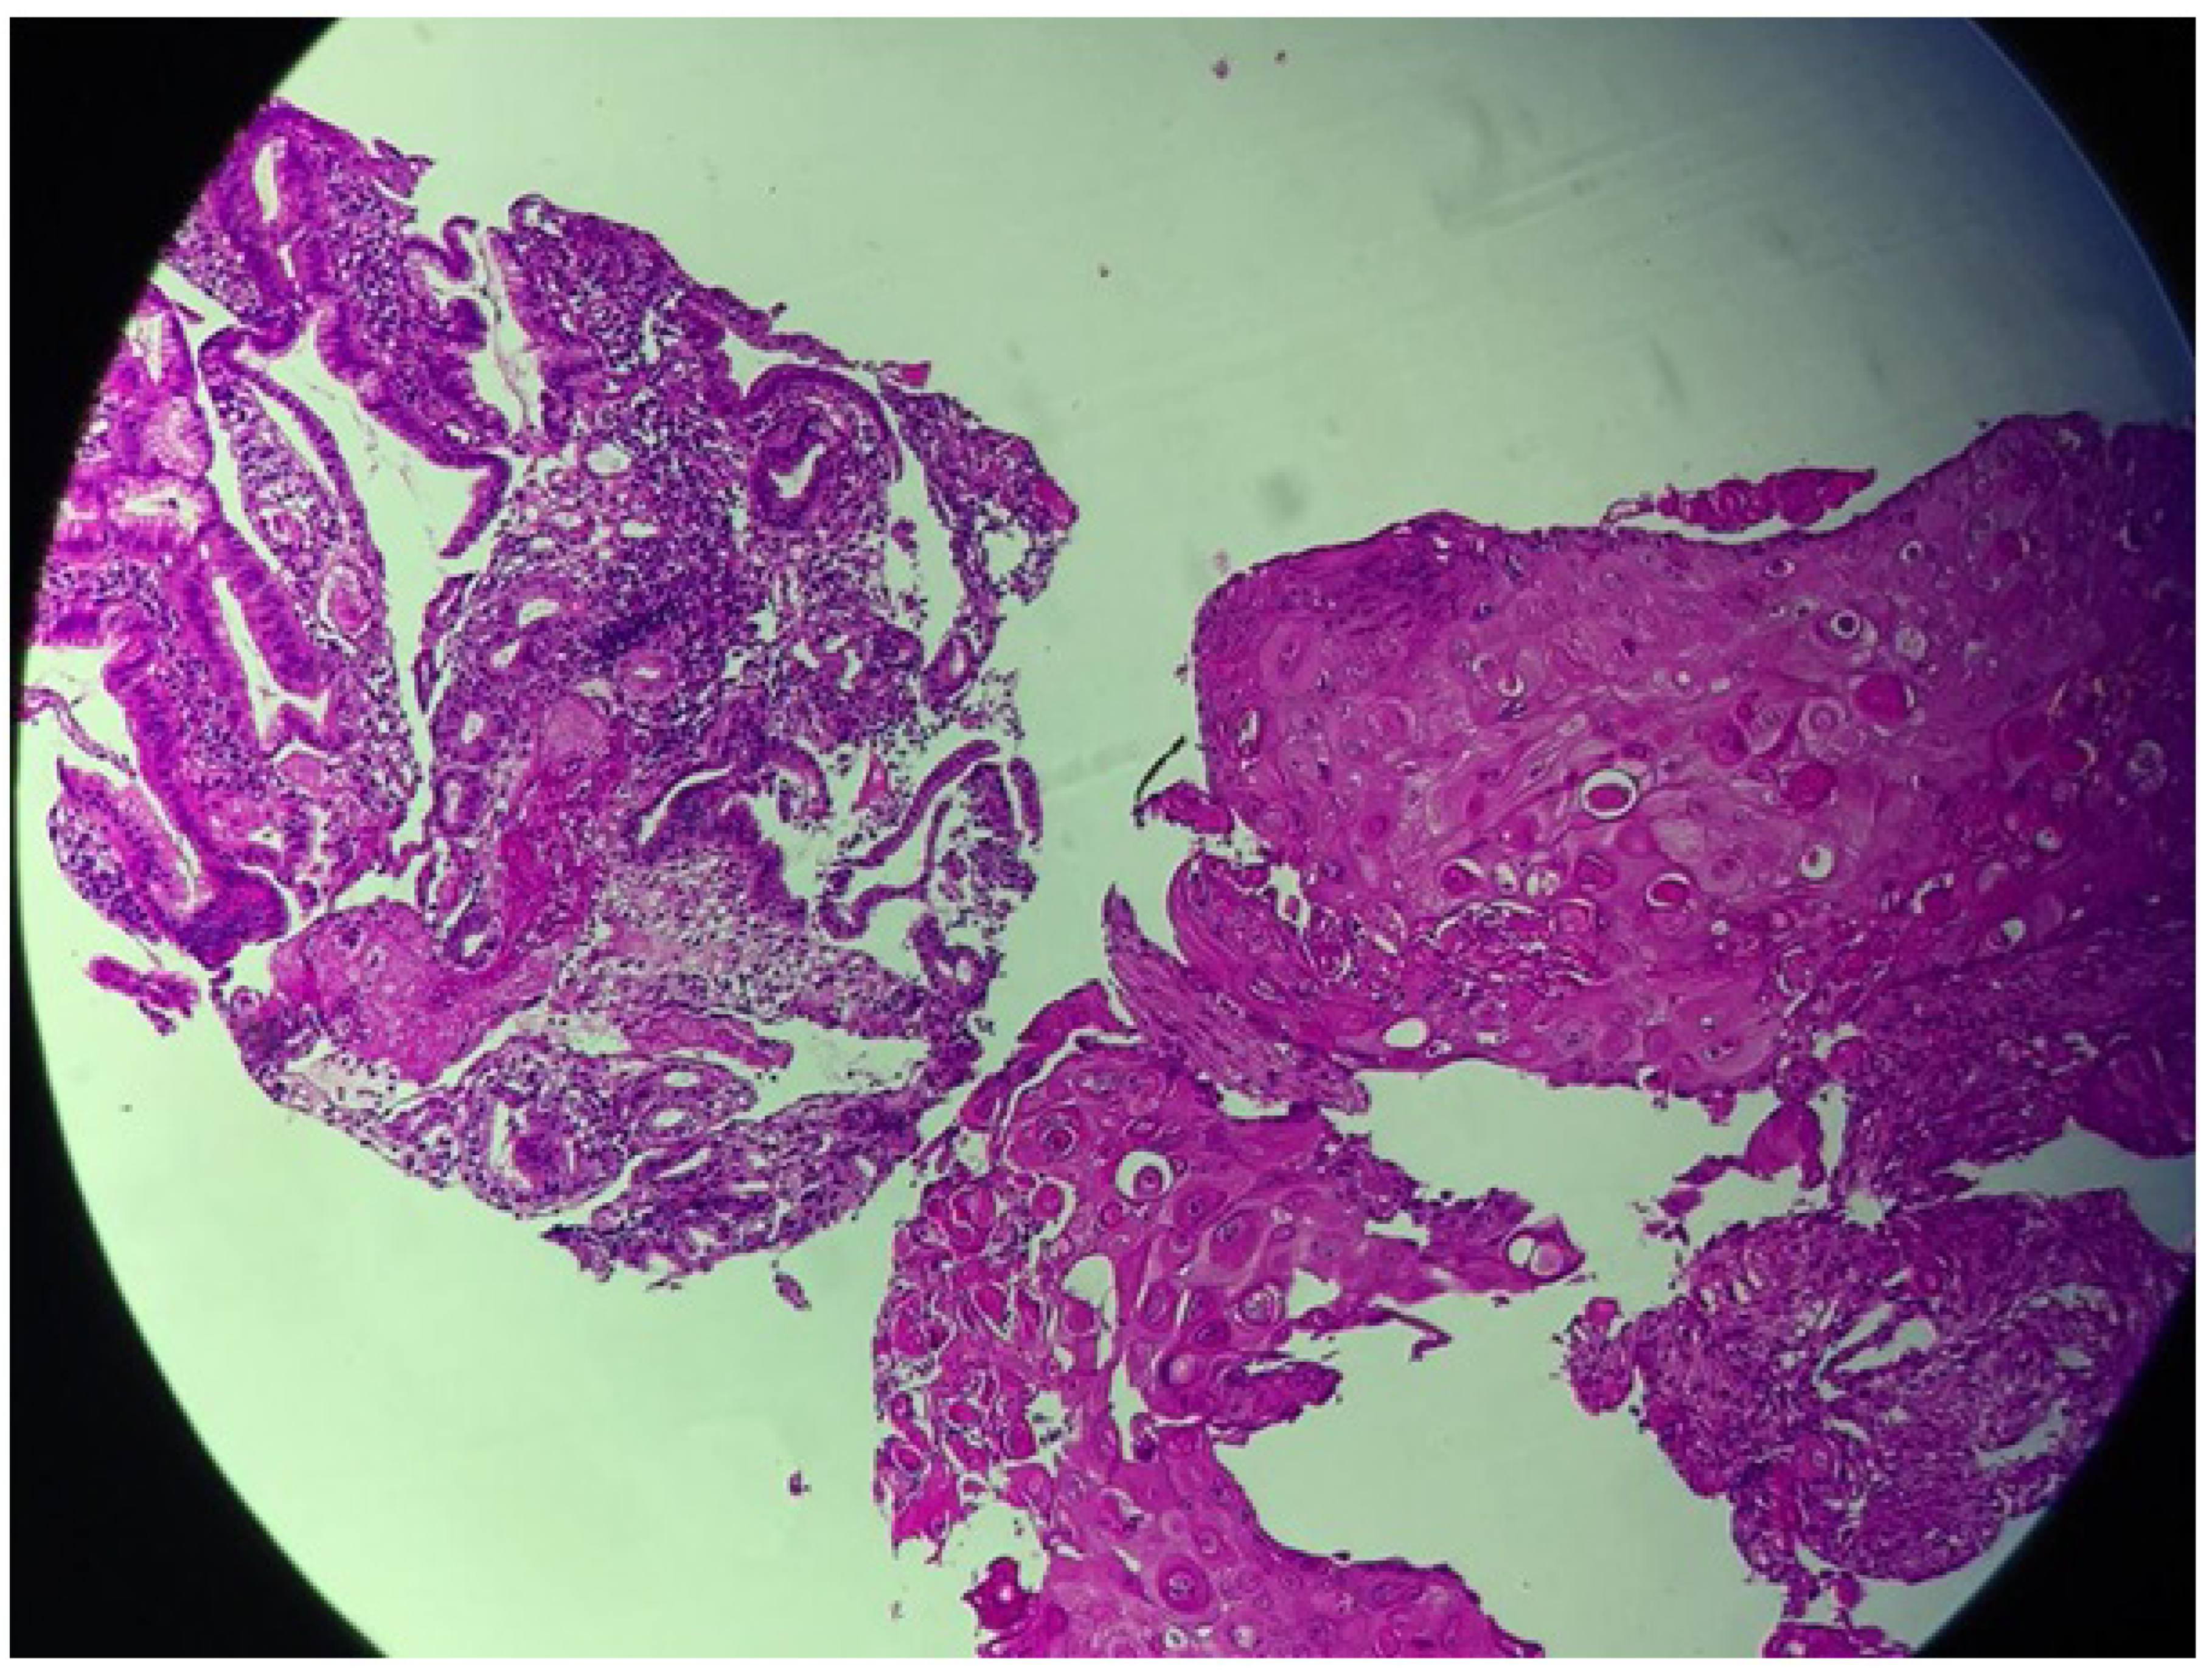

| Diagnosis | Squamous cell carcinoma (SCC) of the gallbladder |